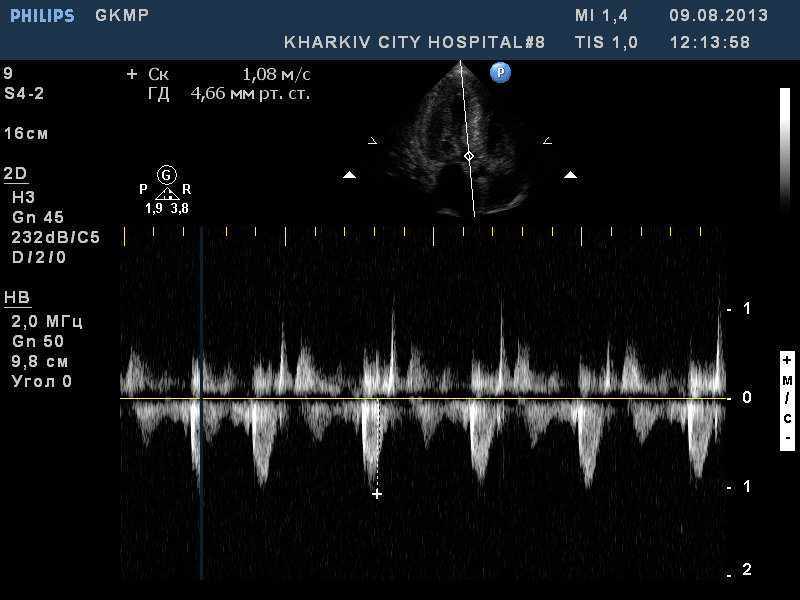

ГКМП

ГКМП. обструкции кровотока в выносящем тракте левого желудочка нет.